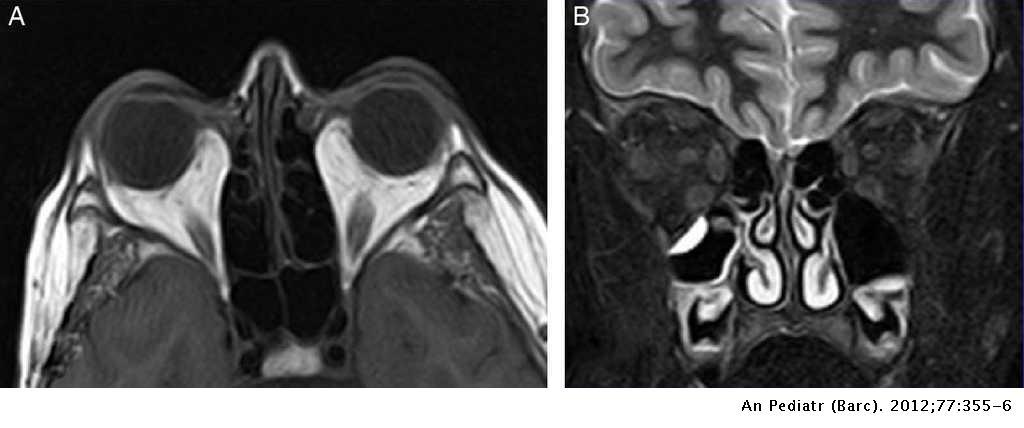

¿Cuáles son los hallazgos radiológicos en la RM de la obitopatía tiroidea?